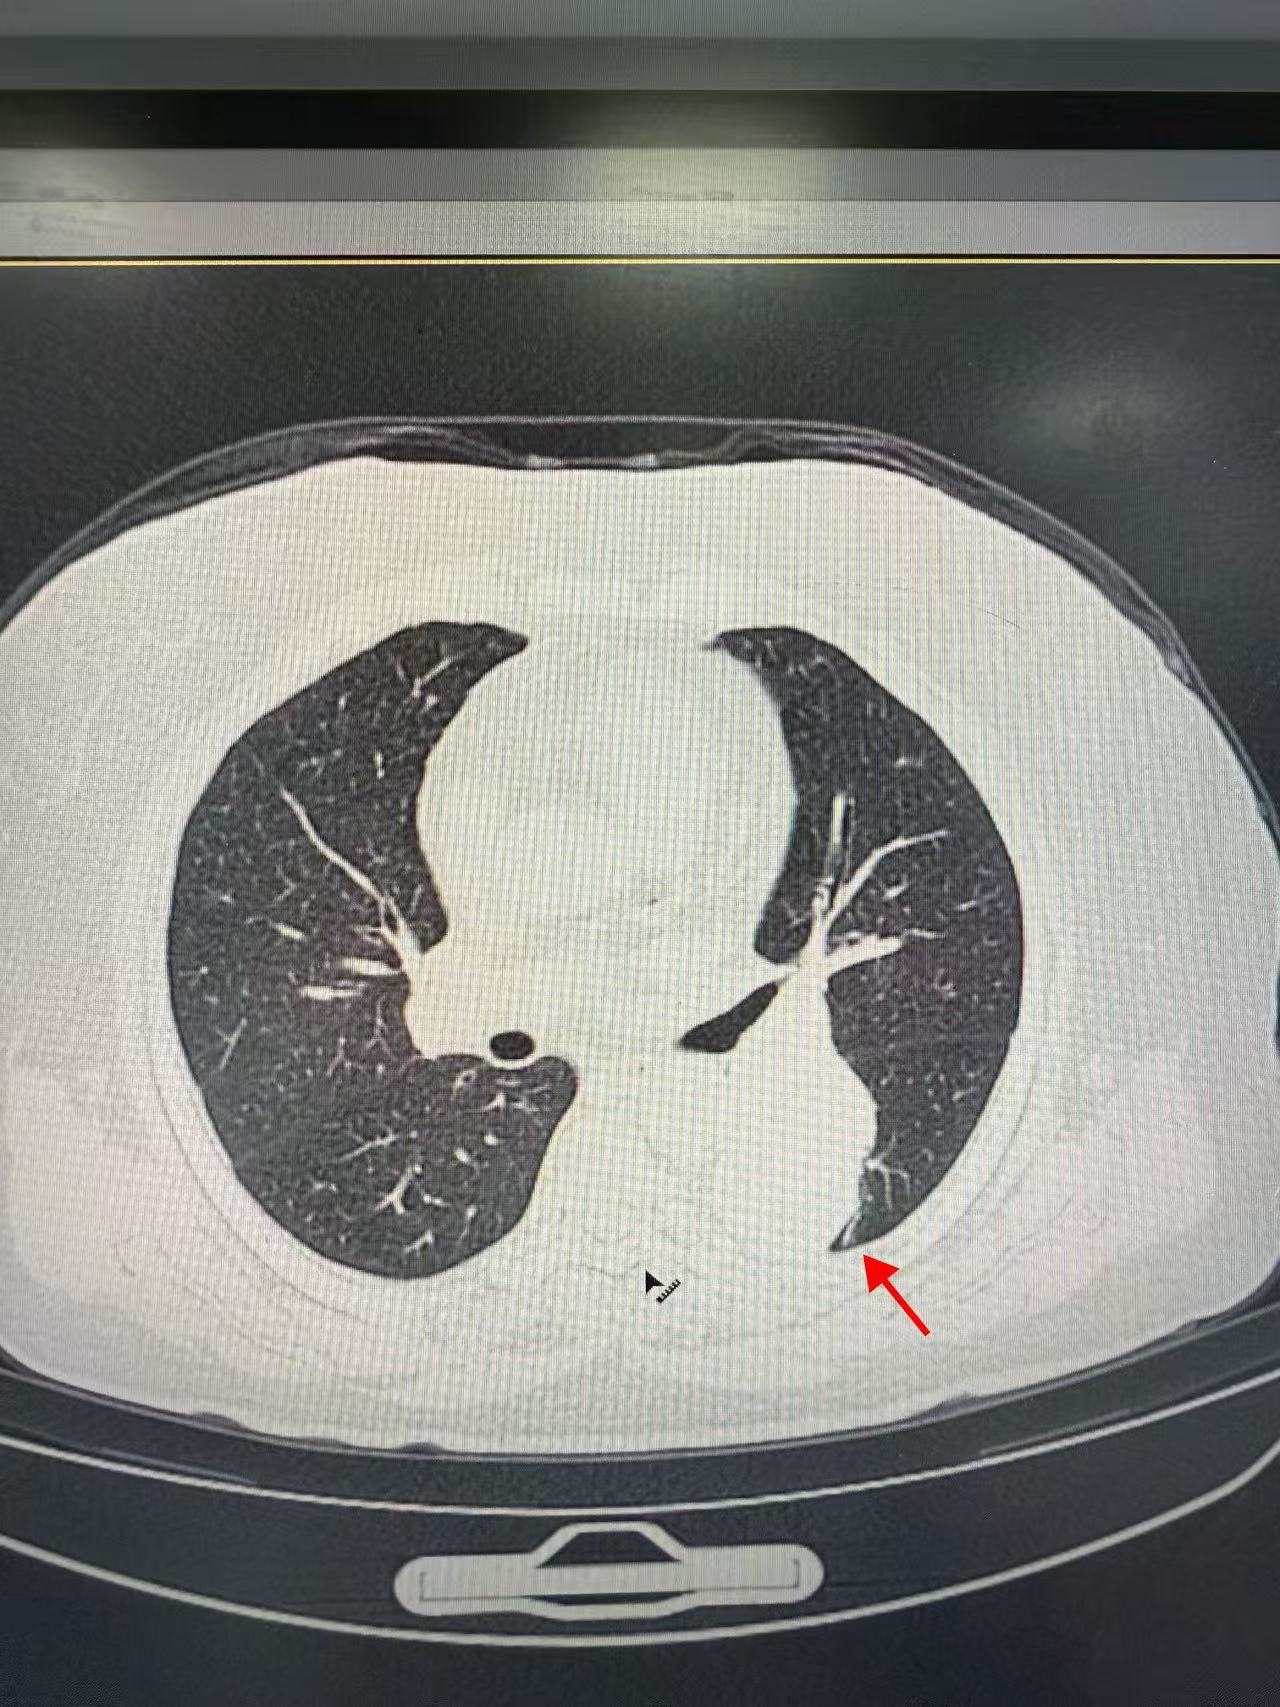

65岁的方女士在常规体检中发现左肺下叶存在一个直径约61×49mm的巨大占位性病变,且位置紧邻肺门,结构关键。

虽然穿刺活检病理初步提示为“较成熟软骨组织及纤维组织,未见恶性肿瘤成分”,由于病灶体积巨大、位置特殊,且穿刺取材范围有限,临床上仍无法完全排除潜在恶性可能。

手术如期进行,周足力教授在胸腔镜探查中,凭借其敏锐的洞察力,发现胸腔内无胸水及胸膜转移,病灶位于左肺下叶背段,突出肺表面,并伴有部分钙化,结合其丰富的临床经验,他高度怀疑为良性错构瘤,术中快速冰冻病理检查结果也证实了其判断——良性病变。